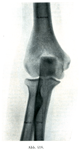

B. 自由上肢の連結